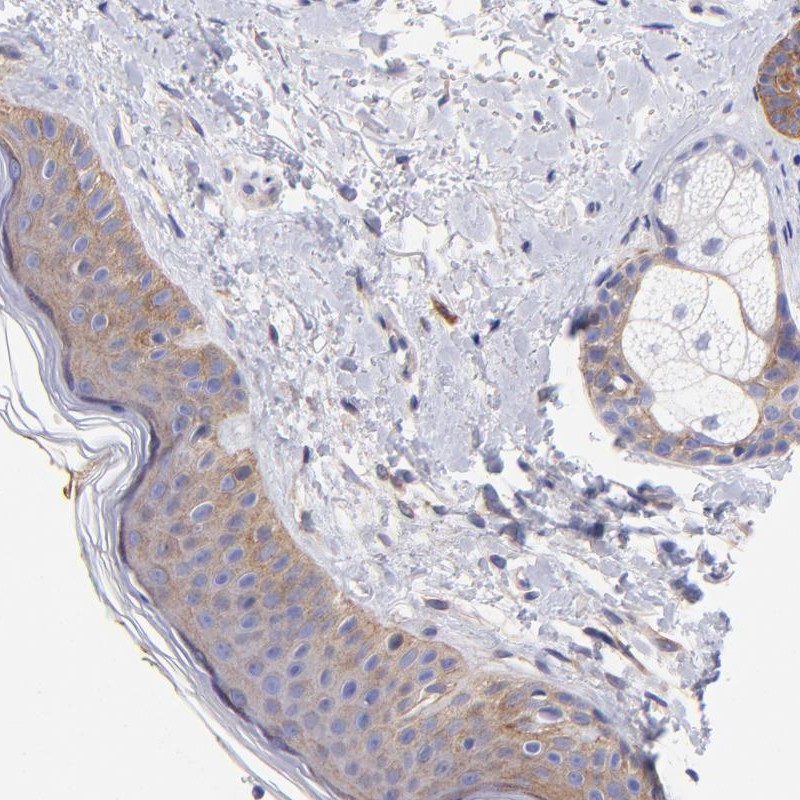

Immunohistochemical staining of human skin shows moderate cytoplasmic positivity in epidermal cells and adnexal cells.